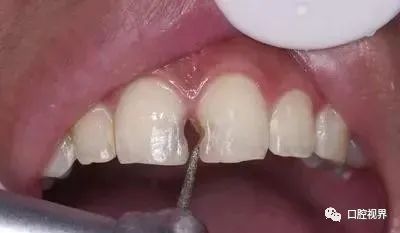

如何解决牙缝大的问题?

早些年,大多都推荐使用牙套,简单快捷,唯一的缺点就是价格稍稍贵点,量力而行吧各位!

此外,贴面修复、烤瓷牙等方法等都可以缓解牙缝过大的问题。(再次强调,不推荐全瓷牙修复,因为那样会损失大量真实牙体,当卸下牙冠你会发现牙缝好像更大了……)

每个人都是独立的个体,所以每个人的具体情况也各不相同,具体问题还得具体分析,如果你需要解决牙缝太大的问题,还得上医院让医生给你好好看看。